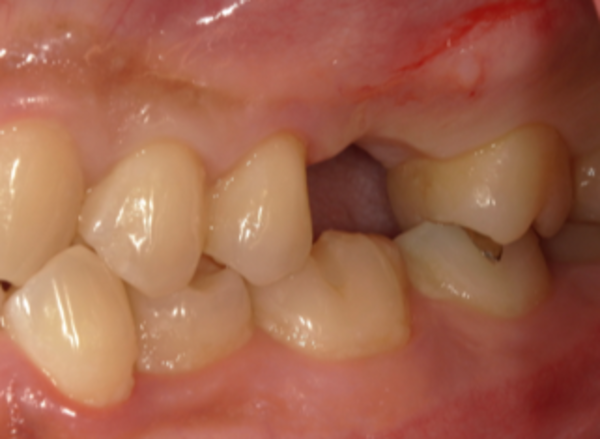

患者様は40代の男性で、左上の奥歯が何もしなくても痛みがあり、温かいもので痛みが強くなるとのことで来院されました。

口腔内診察で左上6番目の歯が縦に割れていることがわかり、破折がどこまで続いているかを判断するためにX線を撮りました。こちらが初診時のX線写真になります。

歯の中央部が縦に破折していることがわかりました。

破折は歯髄腔(歯の神経がある部分)にまで及んでおり、当日は痛みを取るために神経を取る処置を行いました。加えて、歯科顕微鏡で歯の内部や破折部を直接確認しました。

破折は3つある歯根のうち1つに限局していました。